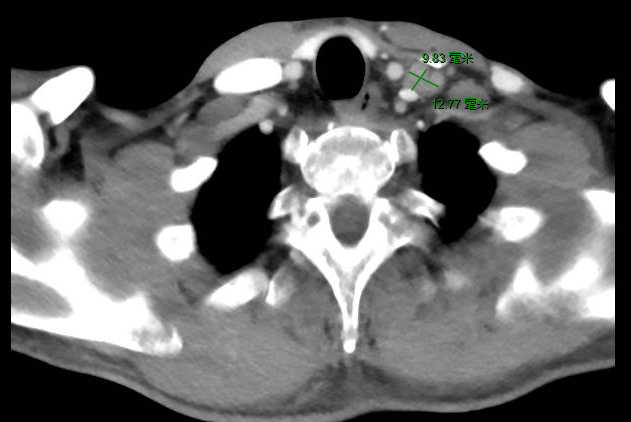

同时发现左颈部和肝脏多发转移灶。

诊断:胃癌术后多发转移(双肺,肝脏,锁骨上淋巴结),Ⅳ期,HER2(+++)。

经影像学评估后,患者肝脏、双肺、颈部淋巴结无进展。

复查:2020.4复查颈部CT及全腹部+盆腔MR大致同前,脑MR示病变较前明显缩小,评估PR。

2020年11月4日复查颈部胸腹盆CT大致同前,脑转移灶明显缩小,继续赫赛汀联合希罗达维持治疗。